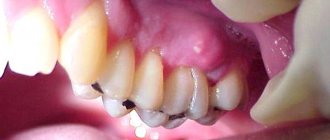

As a rule, the affected areas differ from the healthy surface in their shade, acquiring a brown or chalky color. But the area of ​​their localization is often blocked by the gum, which makes timely diagnosis difficult.

At the same time, the further development of pathology is not always accompanied by the formation of a cavity . The surface of the affected areas is ridged. Probing reveals some softening of the tissue.

Also, when cement caries occurs, general symptoms are noted :

• painful reaction to any irritants: thermal, mechanical, chemical;

• discomfort in the cervical area;

• darkening of the affected areas.